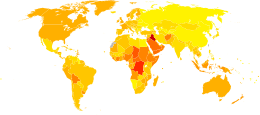

Epidemiology

Multiple myeloma, globally, resulted in about 79,000 deaths in 2013 up from 49,000 in 1990.[7]

United States

In the United States in 2016, there will be an estimated 30,330 new cases and 12,650 deaths.[8] These numbers are based on assumptions made using data from 2011, which estimated the prevalence as 83,367 people, the incidence as 6.1 per 100,000 people per year, and the mortality as 3.4 per 100,000 people per year.

Multiple myeloma is the second most prevalent blood cancer (10%) after non-Hodgkin's lymphoma.[53] It represents approximately 1.8% of all new cancers and 2,1% of all cancer deaths.[8]

Multiple myeloma affects slightly more men than women. African Americans and Native Pacific Islanders have the highest reported incidence of this disease in the United States and Asians the lowest. Results of a recent study found the incidence of myeloma to be 9.5 cases per 100,000 African Americans and 4.1 cases per 100,000 Caucasian Americans. Among African Americans, myeloma is one of the top 10 leading causes of cancer death.

UK

Myeloma is the 17th most common cancer in the UK (around 4,800 people were diagnosed with the disease in 2011), and it is the 16th most common cause of cancer death (around 2,700 people died of it in 2012).[54]